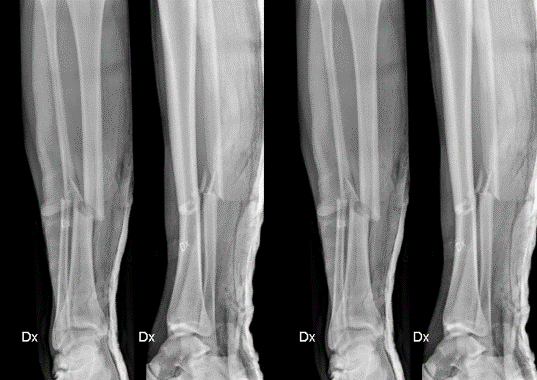

Beskriv frakturen

• HÖGER UNDERBEN

o Mittdiafysär komminut (splittrad) tvärfraktur fibula, dislocerad (halv benbredd)

o Mittdiafysär spiralfraktur tibia, dislocerad (halv benbredd)

o 12-13 cm proximalt om fotleden.